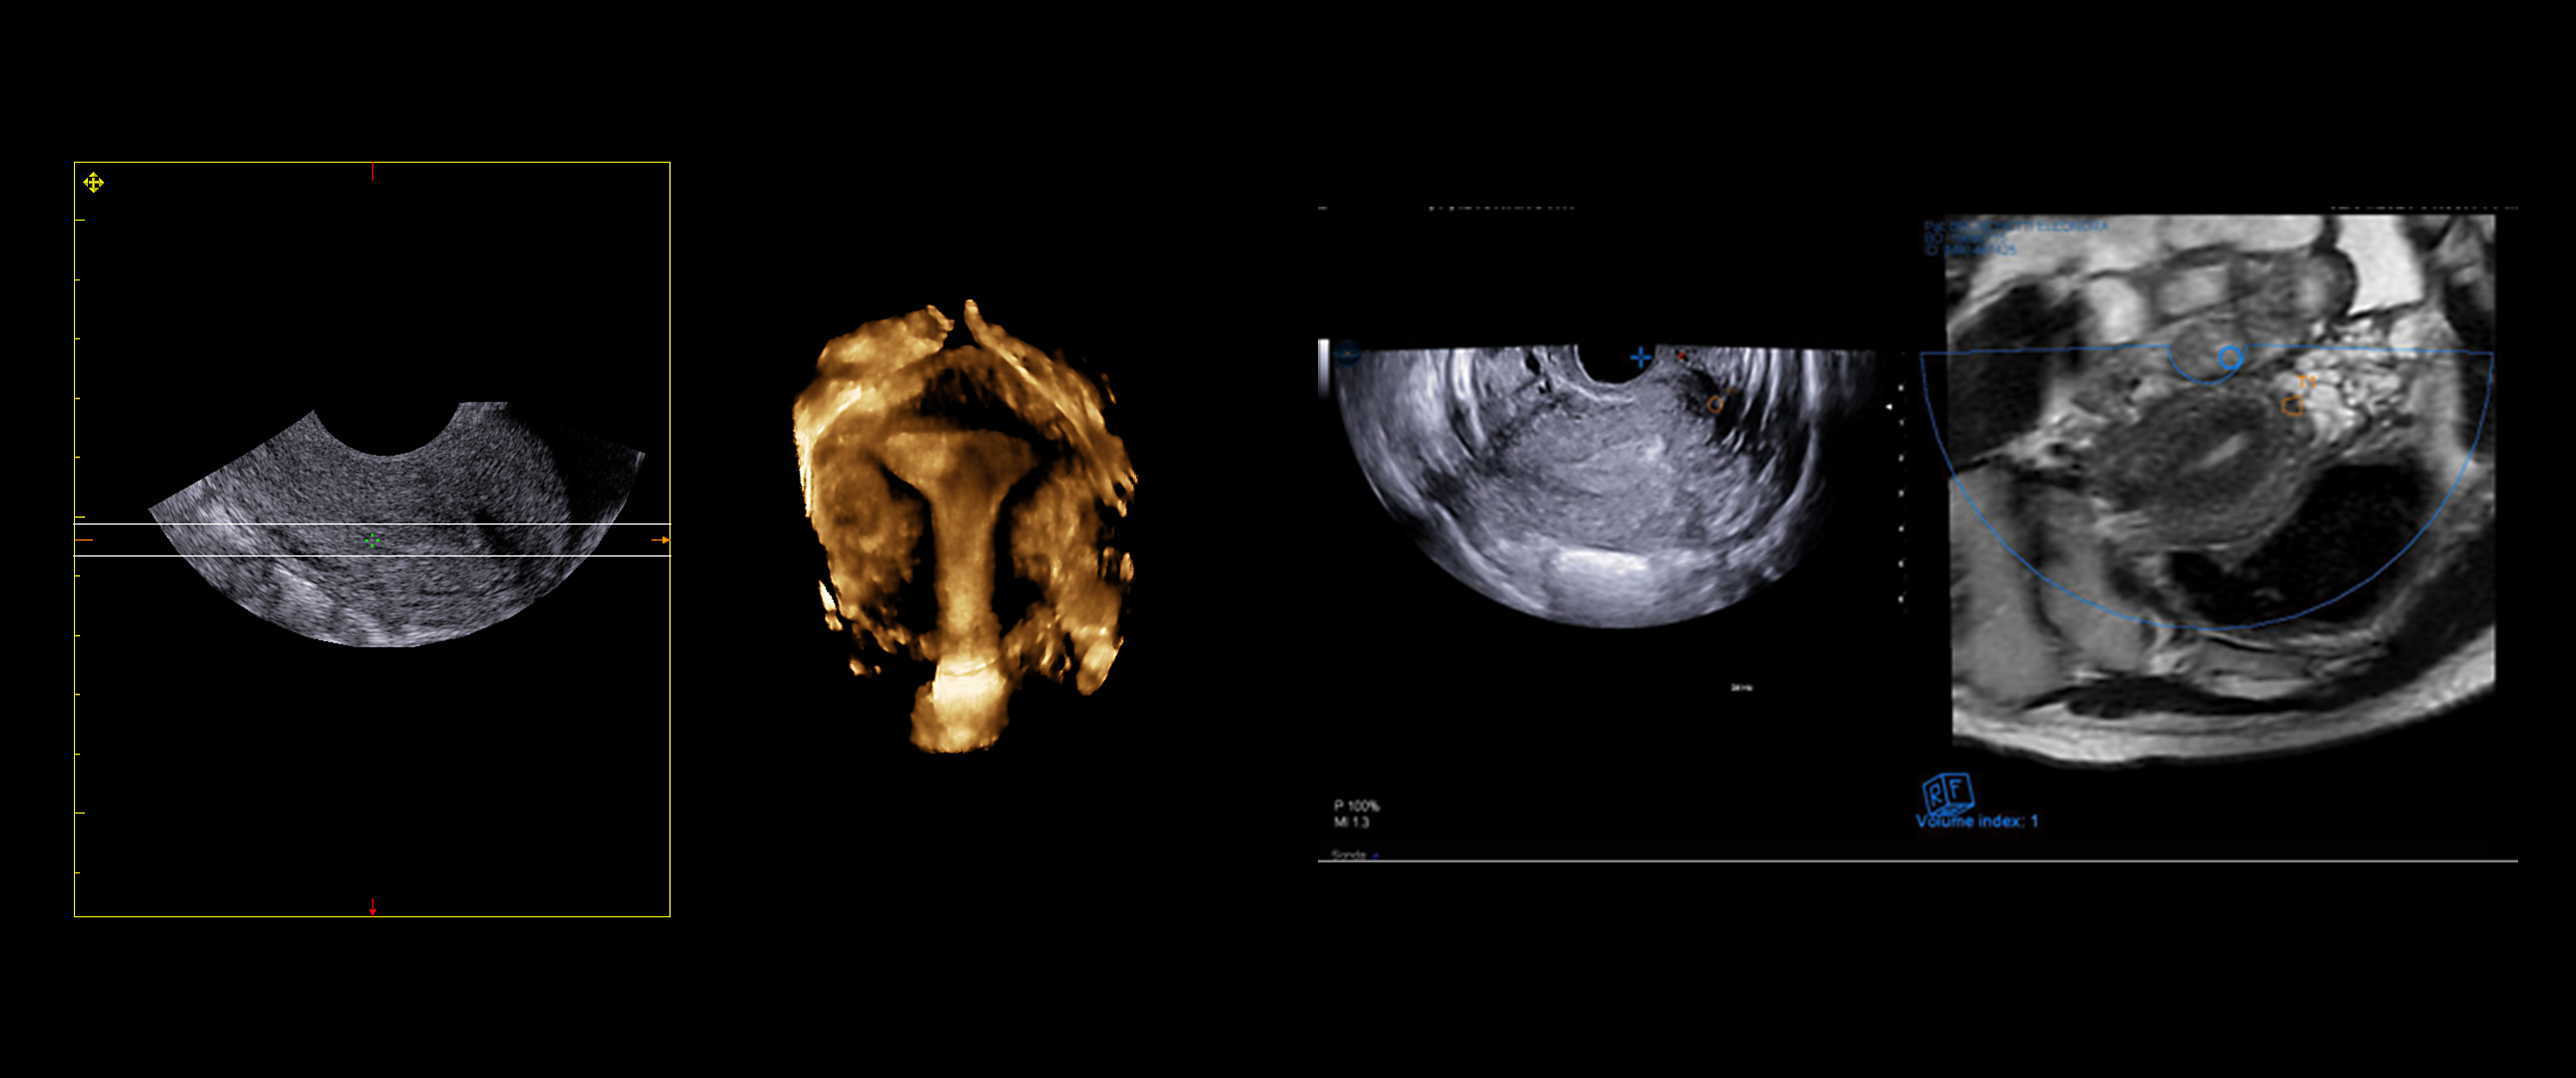

A standard examination very frequently highlights situations that need to be analyzed in greater detail. Esaote’s new volume rendering algorithm offers realistic three-dimensional reconstructions of the internal cavity of the uterus, within a few seconds, for evaluation of uterine shape and size. Thick Slice Imaging (TSI) 3D environment is particularly useful when the purpose is to highlight a well-defined and confined structure, such as the endometrium, allowing for a completely customizable concavity line.

Virtual Navigator is the revolutionary Esaote technology for fusion imaging. Suitable applications for this methodology include deep infiltrating endometriosis (DIE), where the combination of magnetic resonance imaging (MRI) and transvaginal ultrasound (TVUS) considerably optimizes the detection of this pathology.